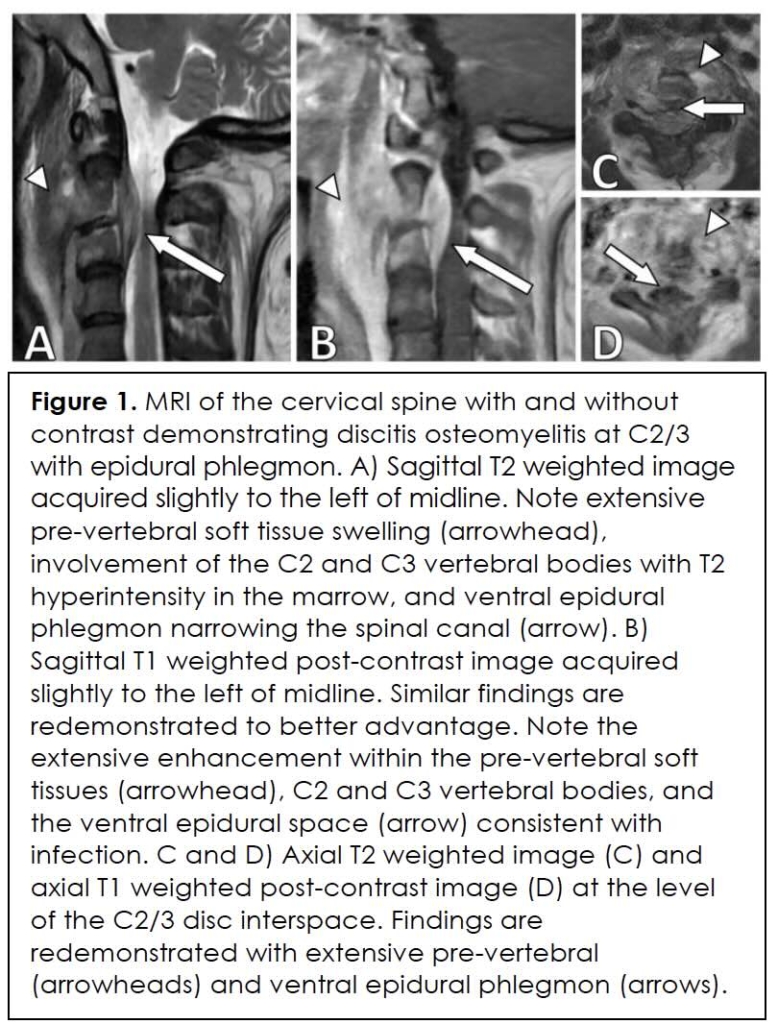

In view of continued deterioration of neck pain and headache, the earlier scheduled cervical spine MRI was performed soon after the ED visit. Imaging revealed abnormal enhancement and edema at C2-C3 vertebral levels with accompanying narrowing of the spinal canal consistent with osteomyelitis and an epidural abscess (Figure 1). Biopsy under CT guidance was confirmed, with cultures showing methicillin-resistant Staphylococcus aureus (MRSA). During this period, inflammatory markers were significantly elevated: white blood cell count 11.2 × 10⁹/L, CRP 7.35 mg/dL, and ESR 114 mm/hr. Thoracic spine MRI revealed additional foci of vertebral osteomyelitis.

Initial investigations focused on ruling out emergent causes of headache, including acute intracranial hemorrhage and venous sinus thrombosis, using MRI of the brain with and without contrast and a CT venogram of the head. Evaluation for increased intracranial pressure included slit-lamp fundoscopic examination and lumbar puncture, which revealed a mildly elevated opening pressure. As her symptoms progressed, particularly with focal neck pain, an MRI of the cervical spine was performed, revealing lesions at the C2-C3 vertebrae. A biopsy and culture confirmed cervical osteomyelitis and an epidural abscess due to methicillin-resistant Staphylococcusaureus (MRSA). Inflammatory markers were not obtained when she first presented but were significantly elevated when the infectious etiology was suspected. Finally, further thoracic MRI revealed no additional lesions.